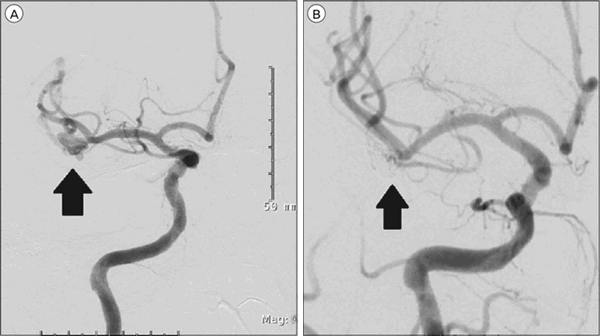

Применяются и эндовазальные (т. е. внутрисосудистые) оперативные вмешательства. Делаются они, как правило, людям преклонного возраста при наличии тяжёлых сопутствующих заболеваний, при труднодоступных аневризмах, при аневризмах, расположенных в чрезвычайно важных функциональных зонах. Они выполняются так: аневризма под контролем рентгена и контрастного вещества заполняется специальными платиновыми микроспиралями, которые «выключают» аневризму из кровотока. Во всём мире в настоящее время всё больше отдают предпочтение именно этому методу: он менее травматичен, даёт меньше осложнений, больные раньше выписываются из стационара. При выполнении ряда эндовазальных вмешательств (для удобства введения в полость аневризмы микроспиралей) могут использоваться специальные стент-ретриверы, которые после выполнения процедуры удаляют.

Как показывает практика Института нейрохирургии имени Бурденко, открытое нейрохирургическое вмешательство даёт надёжный результат в 98 % случаев. То есть больные навсегда избавляются от этой патологии. У эндовазальных операций этот показатель несколько ниже, но тоже достаточно высокий.

Оперативное лечение направлено на предотвращение разрыва аневризмы. Его основными методами являются клипирование шейки аневризмы и эндоваскулярная окклюзия. Может применяться стереотаксическая электрокоагуляция и искусственное тромбирование аневризмы при помощи коагулянтов. В отношении сосудистых мальформаций производят радиохирургическое или транскраниальное удаление АВМ.

· Микрохирургическое клипирование аневризм сосудов головного мозга.

· Эндоваскулярная эмболизация аневризм сосудов головного мозга.

· Выключение аневризмы из кровотока. В ряде случаев выключение из кровотока только купола и тела аневризмы с остаточным кровотоком в области шейки аневризмы.

Слева состояние до операции, справа — после.

Выбор вида оперативного вмешательства зависит от показаний, места локализации, целостности, анатомических особенностей аневризмы сосуда, общего состояния пациента, степени угрозы жизни, технических возможностей нейрохирургического центра. Вмешательство может быть выполнено согласно одной из тактик хирургии.

- Эндоваскулярная операция - в полость сосуда (внутрь) чрескожным доступом (без вскрытия черепной коробки) под рентген-контролем вводится микрокатетер для установки сосудистого стента или спирали. Устройства полностью или субтотально «выключают» артерию из кровотока. Со временем аневризма тромбируется и уменьшается в размерах.

- Микрохирургическая (открытая под контролем микроскопа) - выполняется экономная трепанация черепа с последующим выделением несущей артерии и выполнением окклюзии путем наложения клипсы у основания шейки аневризмы. Клипсирование (сверху сосуда) позволяет пережать аневризматическую шейку, чем исключить из кровотока сосудистый дефект и свести к предельному минимуму вероятность его разрыва.